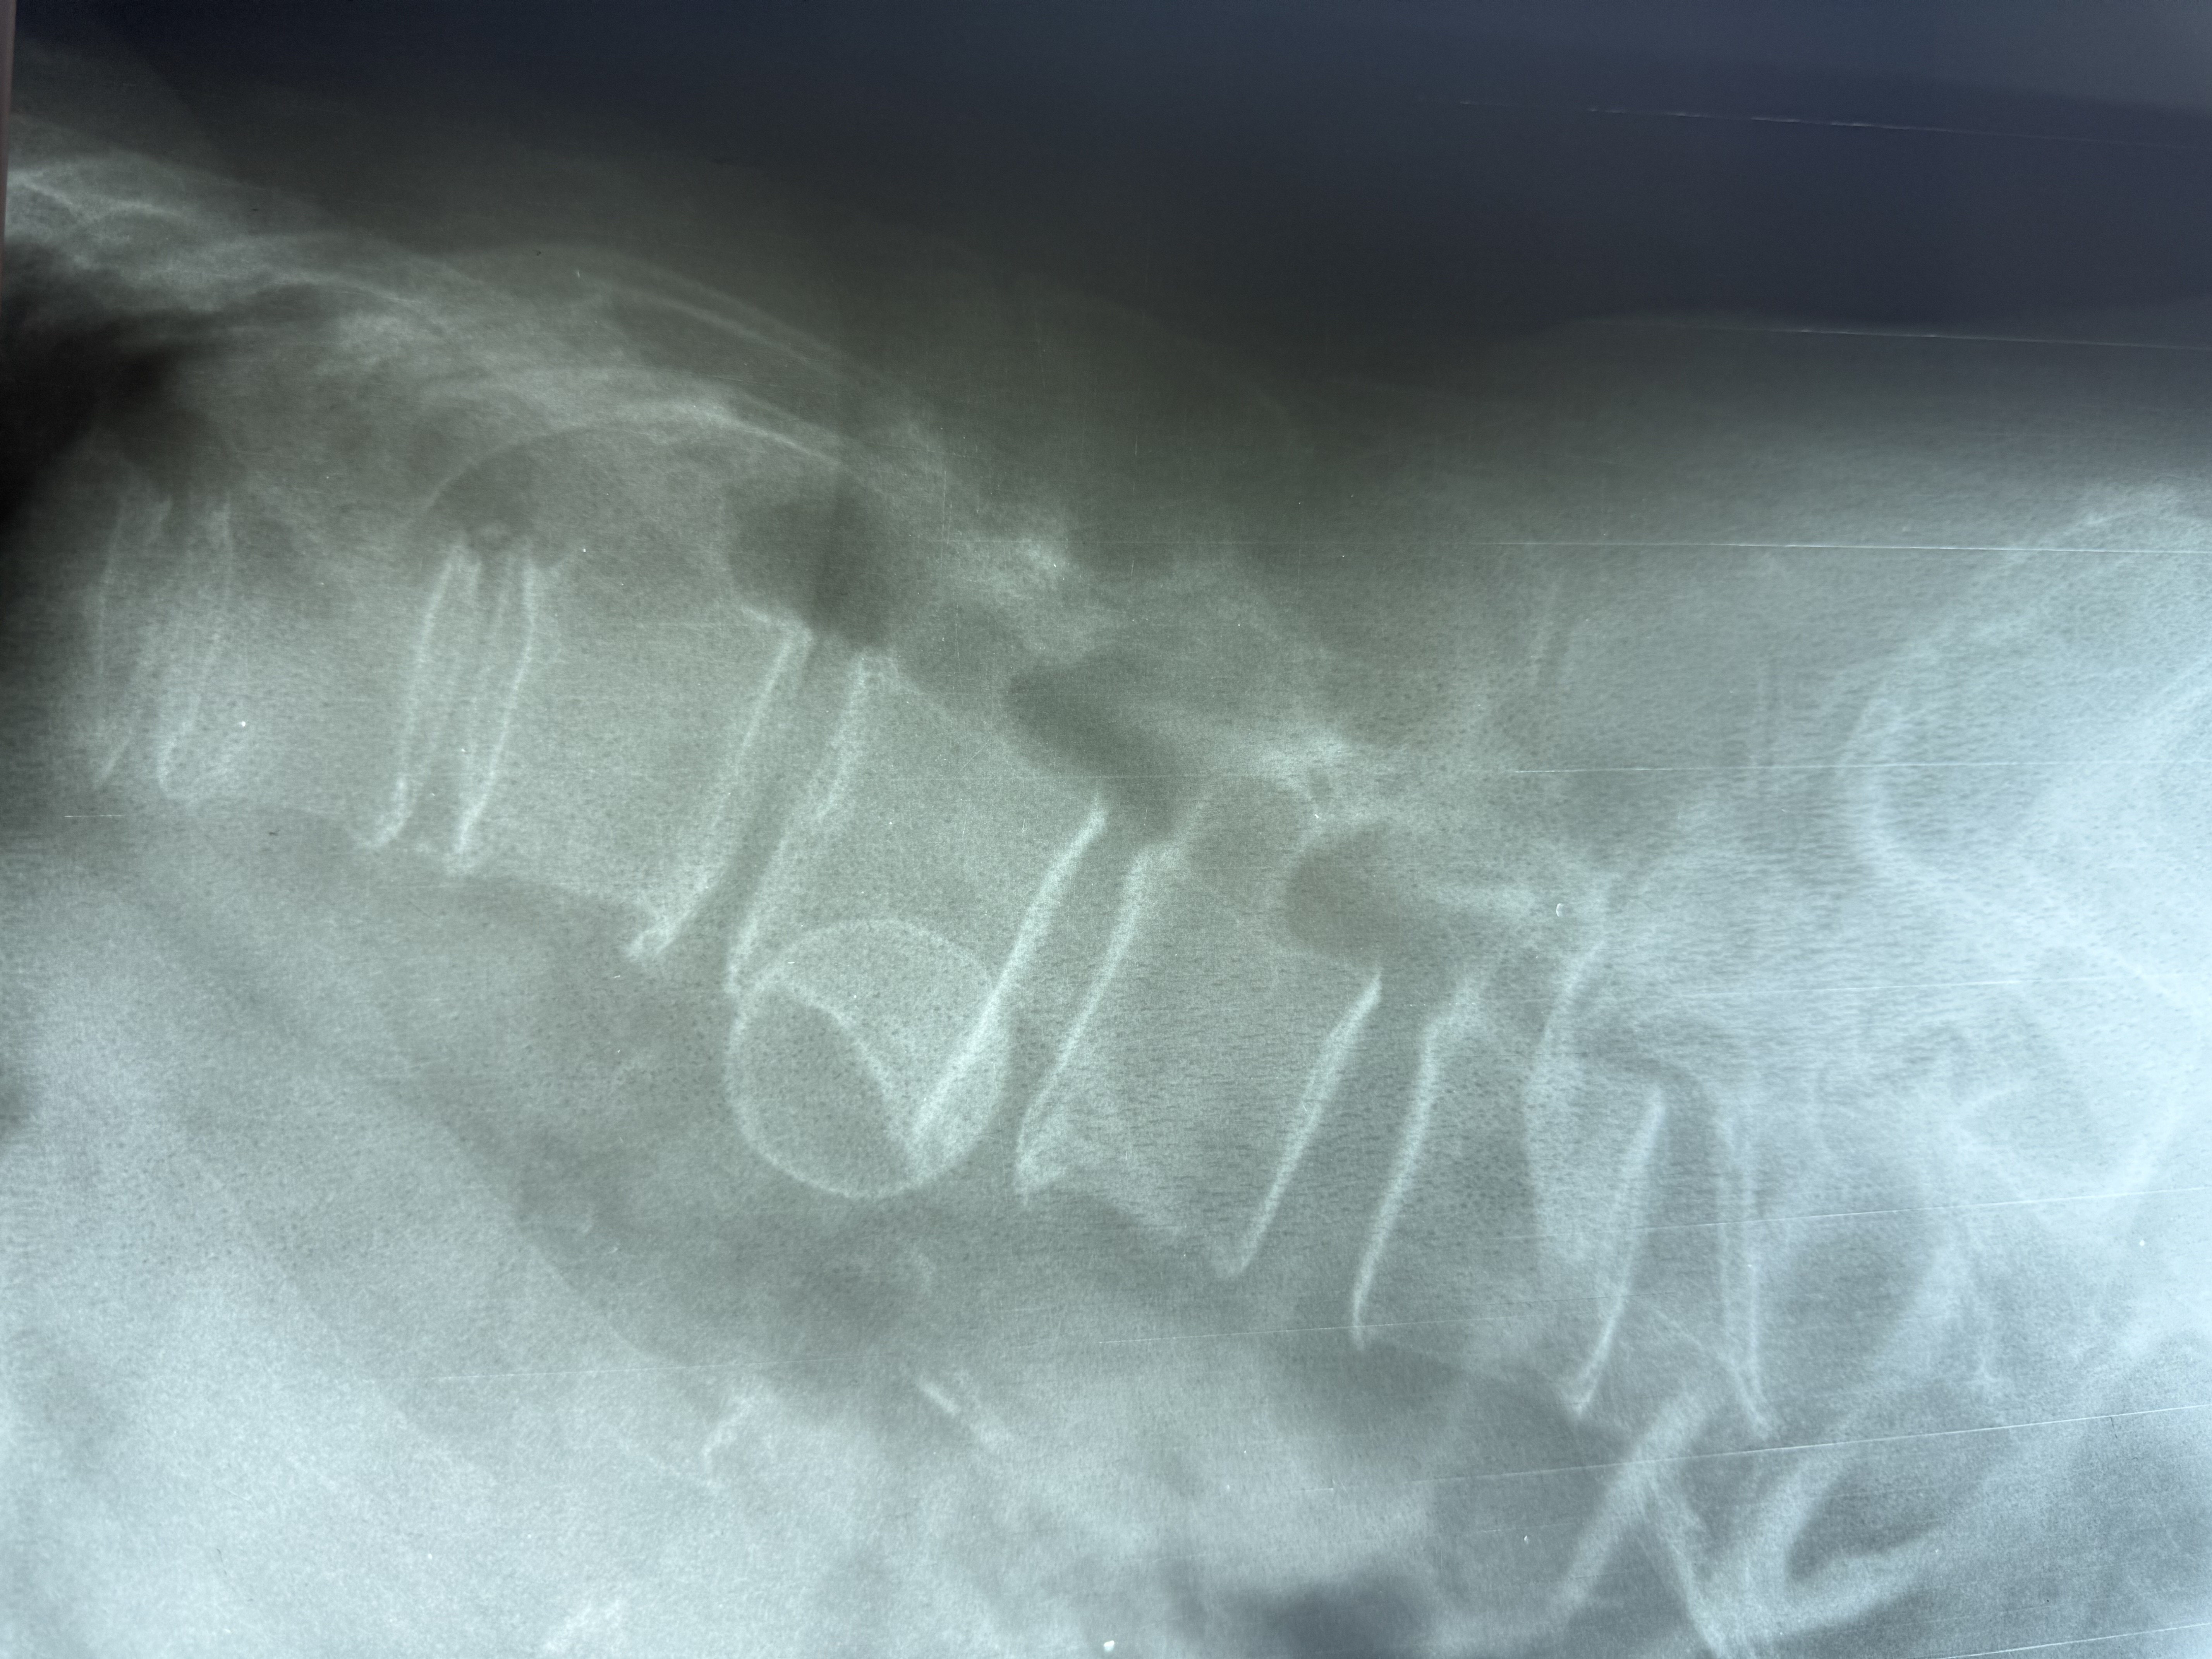

154. Перелом позвонка?

Здравствуйте. Проведена рентгенография грудного отдела позвоночника и выдано заключение "Компрессионный перелом? тела Th4." Скажите, пожалуйста,есть перелом или нет?

Тип: Тема форума

Дата: 23.05.2023 - 15:08